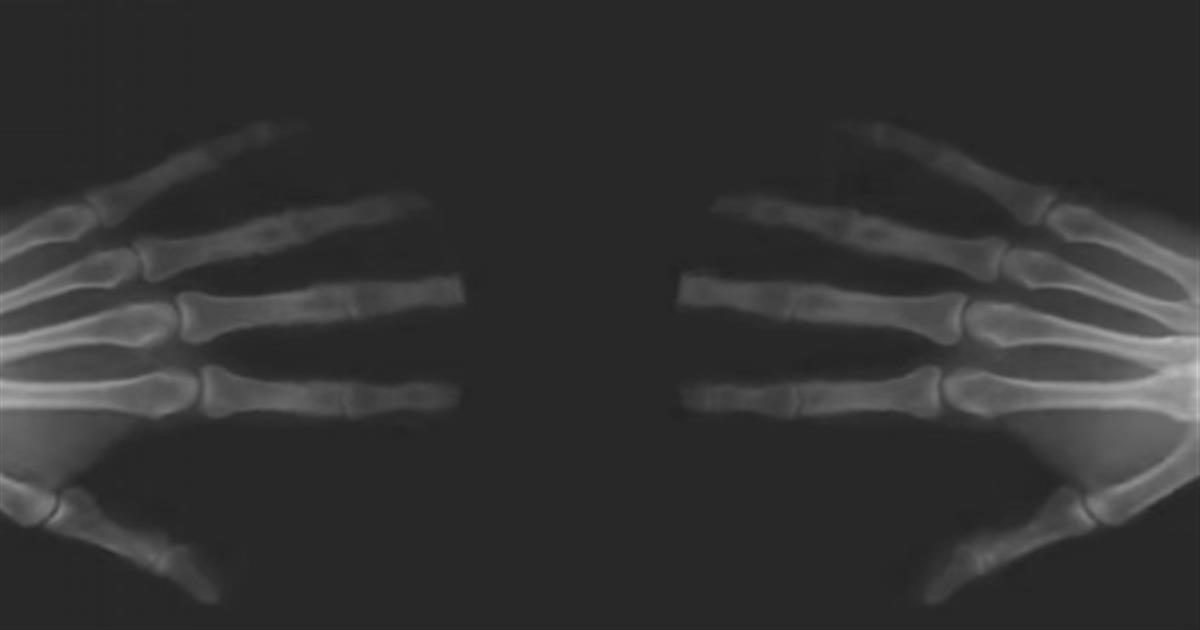

Δάχτυλα: Οι περισσότεροι από εμάς, είτε τυχαία είτε σκοπίμως, τρίζουμε τις αρθρώσεις μας. Εάν όχι τις αρθρώσεις, ίσως έχετε τρίξει τους καρπούς σας, τους αστραγάλους, την πλάτη ή ακόμα και το λαιμό σας. Υπάρχουν δύο ειδών άτομα: Αυτά που λατρεύουν να τρίζουν τις αρθρώσεις τους και εκείνα που δεν αντέχουν ούτε καν στο θόρυβο. Ανεξάρτητα από το πόσο συχνά (ή πόσο σκόπιμα) το κάνετε, ξέρετε τι συμβαίνει στην πραγματικότητα στο σώμα σας;

Ο ήχος που ακούγεται από τις αρθρώσεις σας προκαλείται βασικά από το αρθρικό υγρό που βρίσκεται ανάμεσα στον σύνδεσμό σας. Αυτή η λιπαντική ουσία πρέπει να απελευθερώνεται κάθε φορά που οι αρθρώσεις σας αισθάνονται χαλαρές και άνετα. Όταν δεν έχετε αρθρικό υγρό στις αρθρώσεις, τότε μπορεί να εμφανιστεί δυσκαμψία.

Όταν τεντώσετε την άρθρωση σας – όπως όταν τρίζετε τις αρθρώσεις σας, για παράδειγμα – δημιουργείτε χώρο στο υγρό, το οποίο με τη σειρά του προκαλεί σχηματισμό φυσαλίδων. Οι φυσαλίδες στη συνέχεια καταρρέουν και σκάζουν, προκαλώντας το θόρυβο που ακούγεται. Παράλληλα δείτε πως τα νύχια των ποδιών σας δείχνουν αν πάσχετε από καρκίνο.

Τι γίνεται όταν σηκώνεστε πολύ γρήγορα και ακούτε θόρυβο από τα γόνατά σας; Λοιπόν, αυτό είναι πιθανότατα ο ήχος των τενόντων που ολισθαίνουν μεταξύ των αρθρώσεων ή πάνω από τους μυς. Είναι βλαβερό το τρίξιμο των αρθρώσεων, σκόπιμα ή όχι; Όχι, το τρίξιμο των αρθρώσεων δεν είναι επικίνδυνο.

Πολλές μελέτες έχουν υποστηρίξει αυτόν τον ισχυρισμό, καθώς και ένα 60ετές πείραμα που διενεργήθηκε από τον ερευνητή Donald L. Uger. Για έξι δεκαετίες, αυτός ο αφοσιωμένος άντρας έτριζε μόνο τις αρθρώσεις του από το ένα του χέρι και όχι από το άλλο. Το έκανε αυτό για να δει αν το ένα του χέρι θα αναπτύξει περισσότερη αρθρίτιδα από το άλλο.

Μετά από 60 χρόνια, ο Uger είχε την ίδια ποσότητα αρθρίτιδας και στα δύο χέρια, αποδεικνύοντας ουσιαστικά ότι το τρίξιμο δεν επηρεάζει τις αρθρώσεις αρνητικά ή θετικά. Ενώ οι περισσότερες μελέτες συμφωνούν με τα ευρήματα του Uger, υπάρχει μια αντίφαση.

Μια μελέτη του 1990 του Jorge Castellanos και του David Axelrod που ονομάζεται Annuals of Rheumatic Diseases, διαπίστωσε ότι το συχνό τρίξιμο των αρθρώσεων μπορεί να οδηγήσει σε πρήξιμο των χεριών και μείωση της λειτουργίας των αρθρώσεων.

Ωστόσο, δεν έχουν εκδοθεί μελέτες για την υποστήριξη αυτών των ισχυρισμών. Σε γενικές γραμμές λοιπόν, δεν είναι υπερβολικά κακό αλλά όχι και υπερβολικά καλό το τρίξιμο των αρθρώσεων.